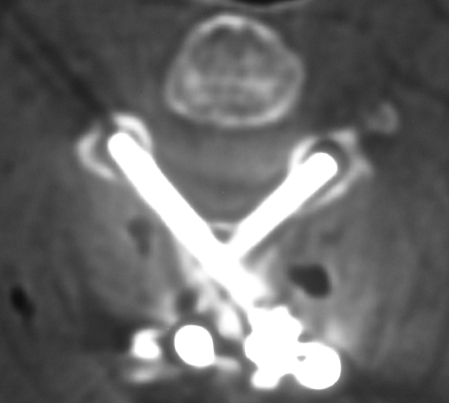

Güncel Servikal MRG - Os Odontoideum ve C1 Kayması

Resim 2: T2 ağırlıklı servikal MRG'de dens'in C2 gövdesinden ayrışarak kranial ve hafifçe posterior yönde deplase olduğu, C1 (atlas) ön arkusunun ise hafifçe geriye kayarak densin bulunması gereken lokalizasyona geldiği görülmektedir. C6 ve C7 vertebra gövdeleri füzyonlu, C5-C6 diskinde ise bulging mevcuttur.